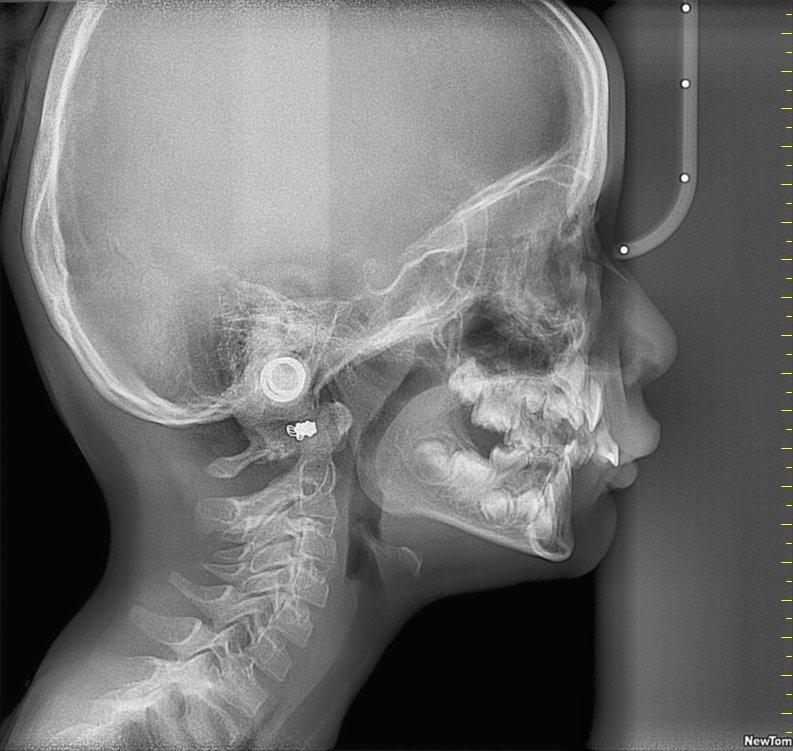

Cephalometric X-Rays

Used in orthodontics to assess jaw alignment and growth patterns.